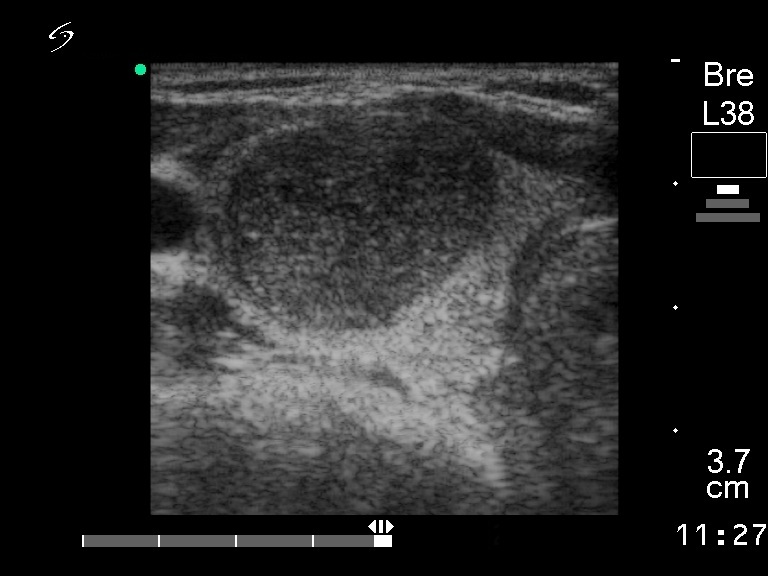

Ultrasonography: a solitary hypoechogenic nodule in the right lobe with a halo sign and perinodular blood flow.